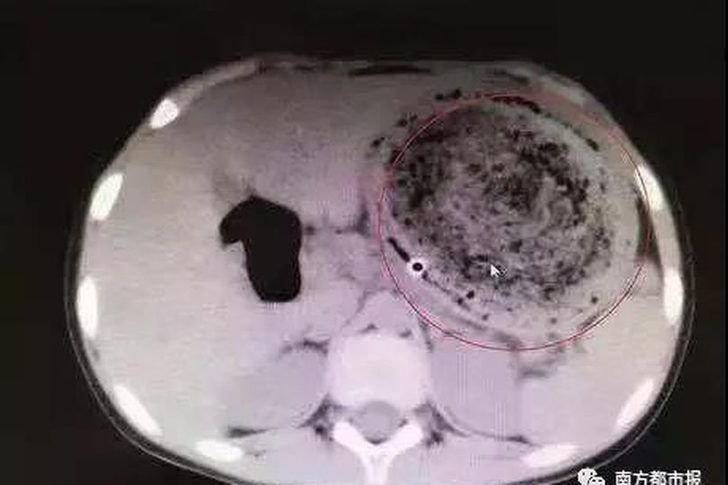

Yapılan tetkikler üzerine kitlenin dalak, pankreas ve kalın bağırsağıyla birlikte böbrek üstü bezlerini de içine aldığı ve boyutlarının eninin 35, boyunun ise 25 santimetre olduğu tespit edilen tümörün ağırlığının ise 8 kilo olduğu anlaşıldı. Genç'e bağ dokusundan kaynaklanan ve nadir görülen bir kanser türü olan sarkom hastalığı teşhisi konuldu. Genç, İzmir Şehir Hastanesi Gastroenteroloji Cerrahi Uzmanı Doç. Dr. Ali Kemal Kayapınar ve Cerrahi Onkoloji Uzmanı Doç. Dr. Murat Güner tarafından 19 Mart'ta yapılan operasyonla sağlığına kavuştu.

Tümörün dalağı, pankreası, sol böbreği ve sol kolonu tuttuğunu anlatan Doç. Dr. Kayapınar şöyle devam etti:

"Tümör ile bu organları çıkardık. Aynı zamanda tümörün içinden altından giden önemli damarı koruyarak geride hiç tümör dokusu bırakmadık. Tümörü çıkardık ve tartıp 8 kilo ağırlığında olduğunu gördük. Hastamızın bu ameliyatla yaşam süresini uzatma olasılığını sağladığımız için gururluyuz. Bu kitle karnın arka tarafında yer aldığı için büyük boyutlara gelene kadar kendini göstermemiş ve hastada herhangi bir şikayet olmamış. Hastanın genç olması bu şişkinliği önemsememesine neden olmuş. Daha sonra organlarına bası yapması sonucu şikayetlerin başlaması üzerine tetkik için doktora gidip hastalığı tesadüfen ortaya çıkmış."